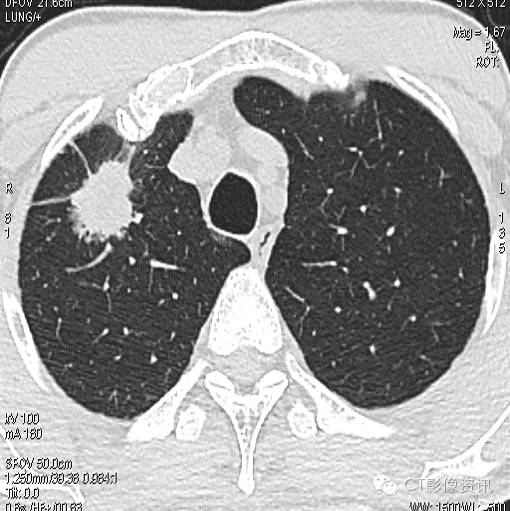

病例3

NIC结果:中央区0.17,周围区:0.12